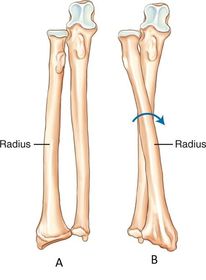

AP no rotation radius and ulna partially superimposed

AP Lateral Rotation separation of radius and ulna

AP Medial Rotation superimposed radius and ulna

A. Supination B. Pronation